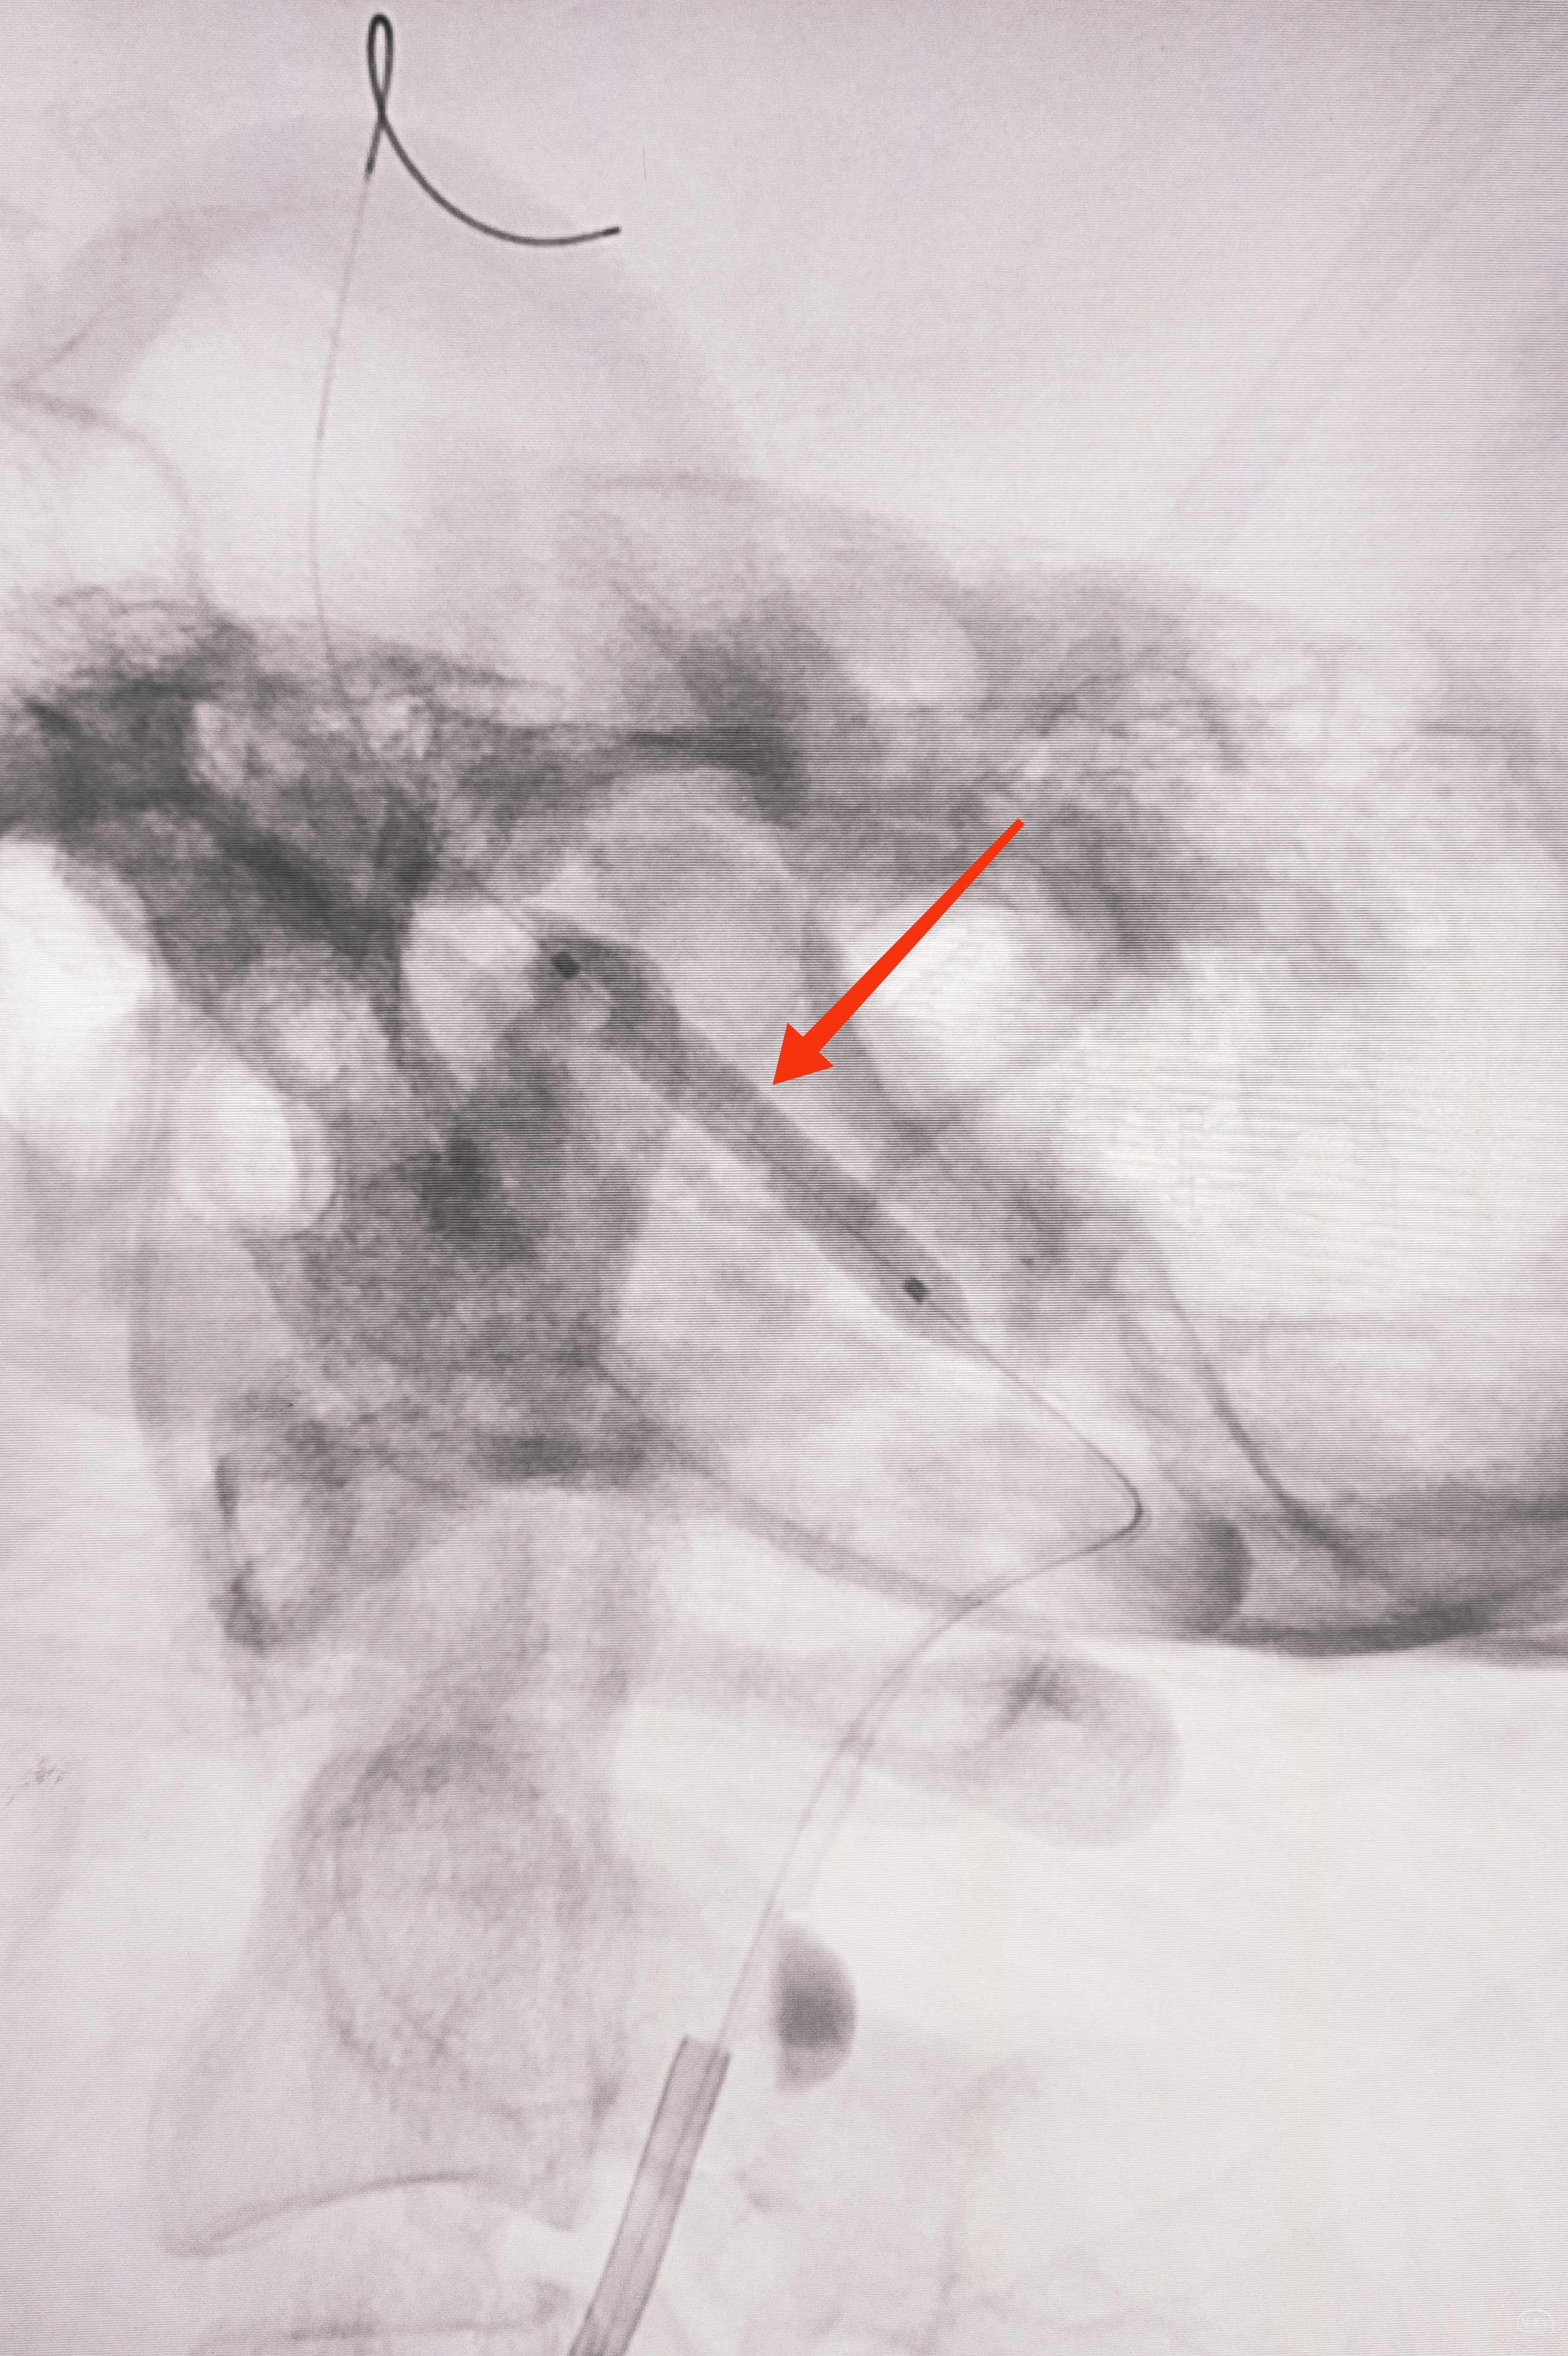

艰苦卓绝的吃线过程,此处心中浮现出一万个草泥马,最终,多角度+超选造影,验证真腔

小球囊+大球囊,梯度预扩

6F导引导管造影确认支架置入部位

支架导引导管内先通过,再回撤技术,顺利释放雅培9×29球扩支架